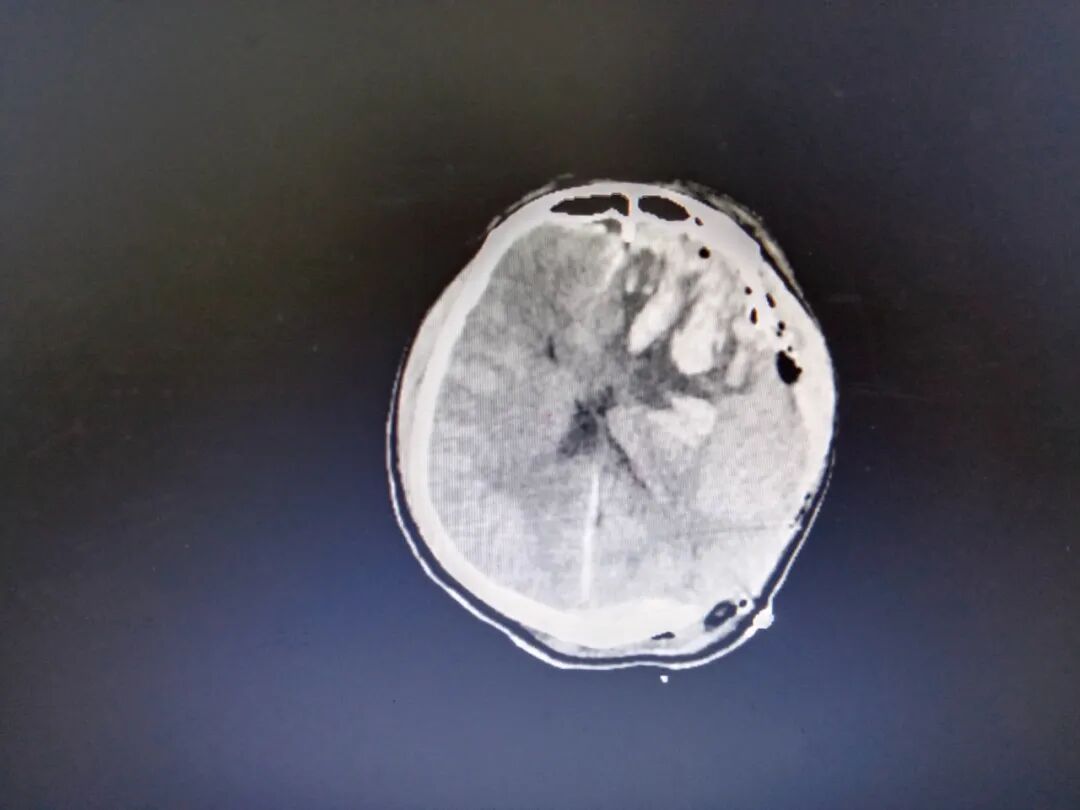

图左侧额颞顶硬膜下血肿

患者呈开放性颅脑损伤重型、颅内多发血肿、左侧脑疝,情况十分危急,甚至在手术麻醉前血压一度低至60/40mmHg。并且患者本身患有高度脂血症和严重的骨质疏松,严重影响了人体的凝血能力,大大增加了手术难度。在经过一个上午的手术,患者脑内血肿清除,血压恢复平稳,放大的瞳孔恢复正常,并有光反应,随后被送至ICU进行观察。